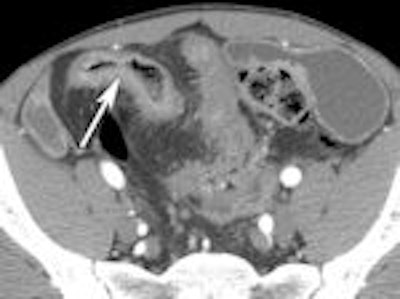

A 2007 study by University of Michigan gastroenterologist Dr. Peter D.R. Higgins showcases the diagnostic power of CT enterography (CTE) for evaluating small bowel Crohn's disease.

Higgins concluded that CTE offered complementary information about symptoms of obstruction in Crohn's disease (Inflammatory Bowel Diseases, March 2007; Vol. 14:3, pp. 262-268).

The following images from Higgins' study illustrate some of the clinically relevant findings about Crohn's disease that can be made with CTE.

Left: Mucosal enhancement. Right: Increased mesenteric vascularity.